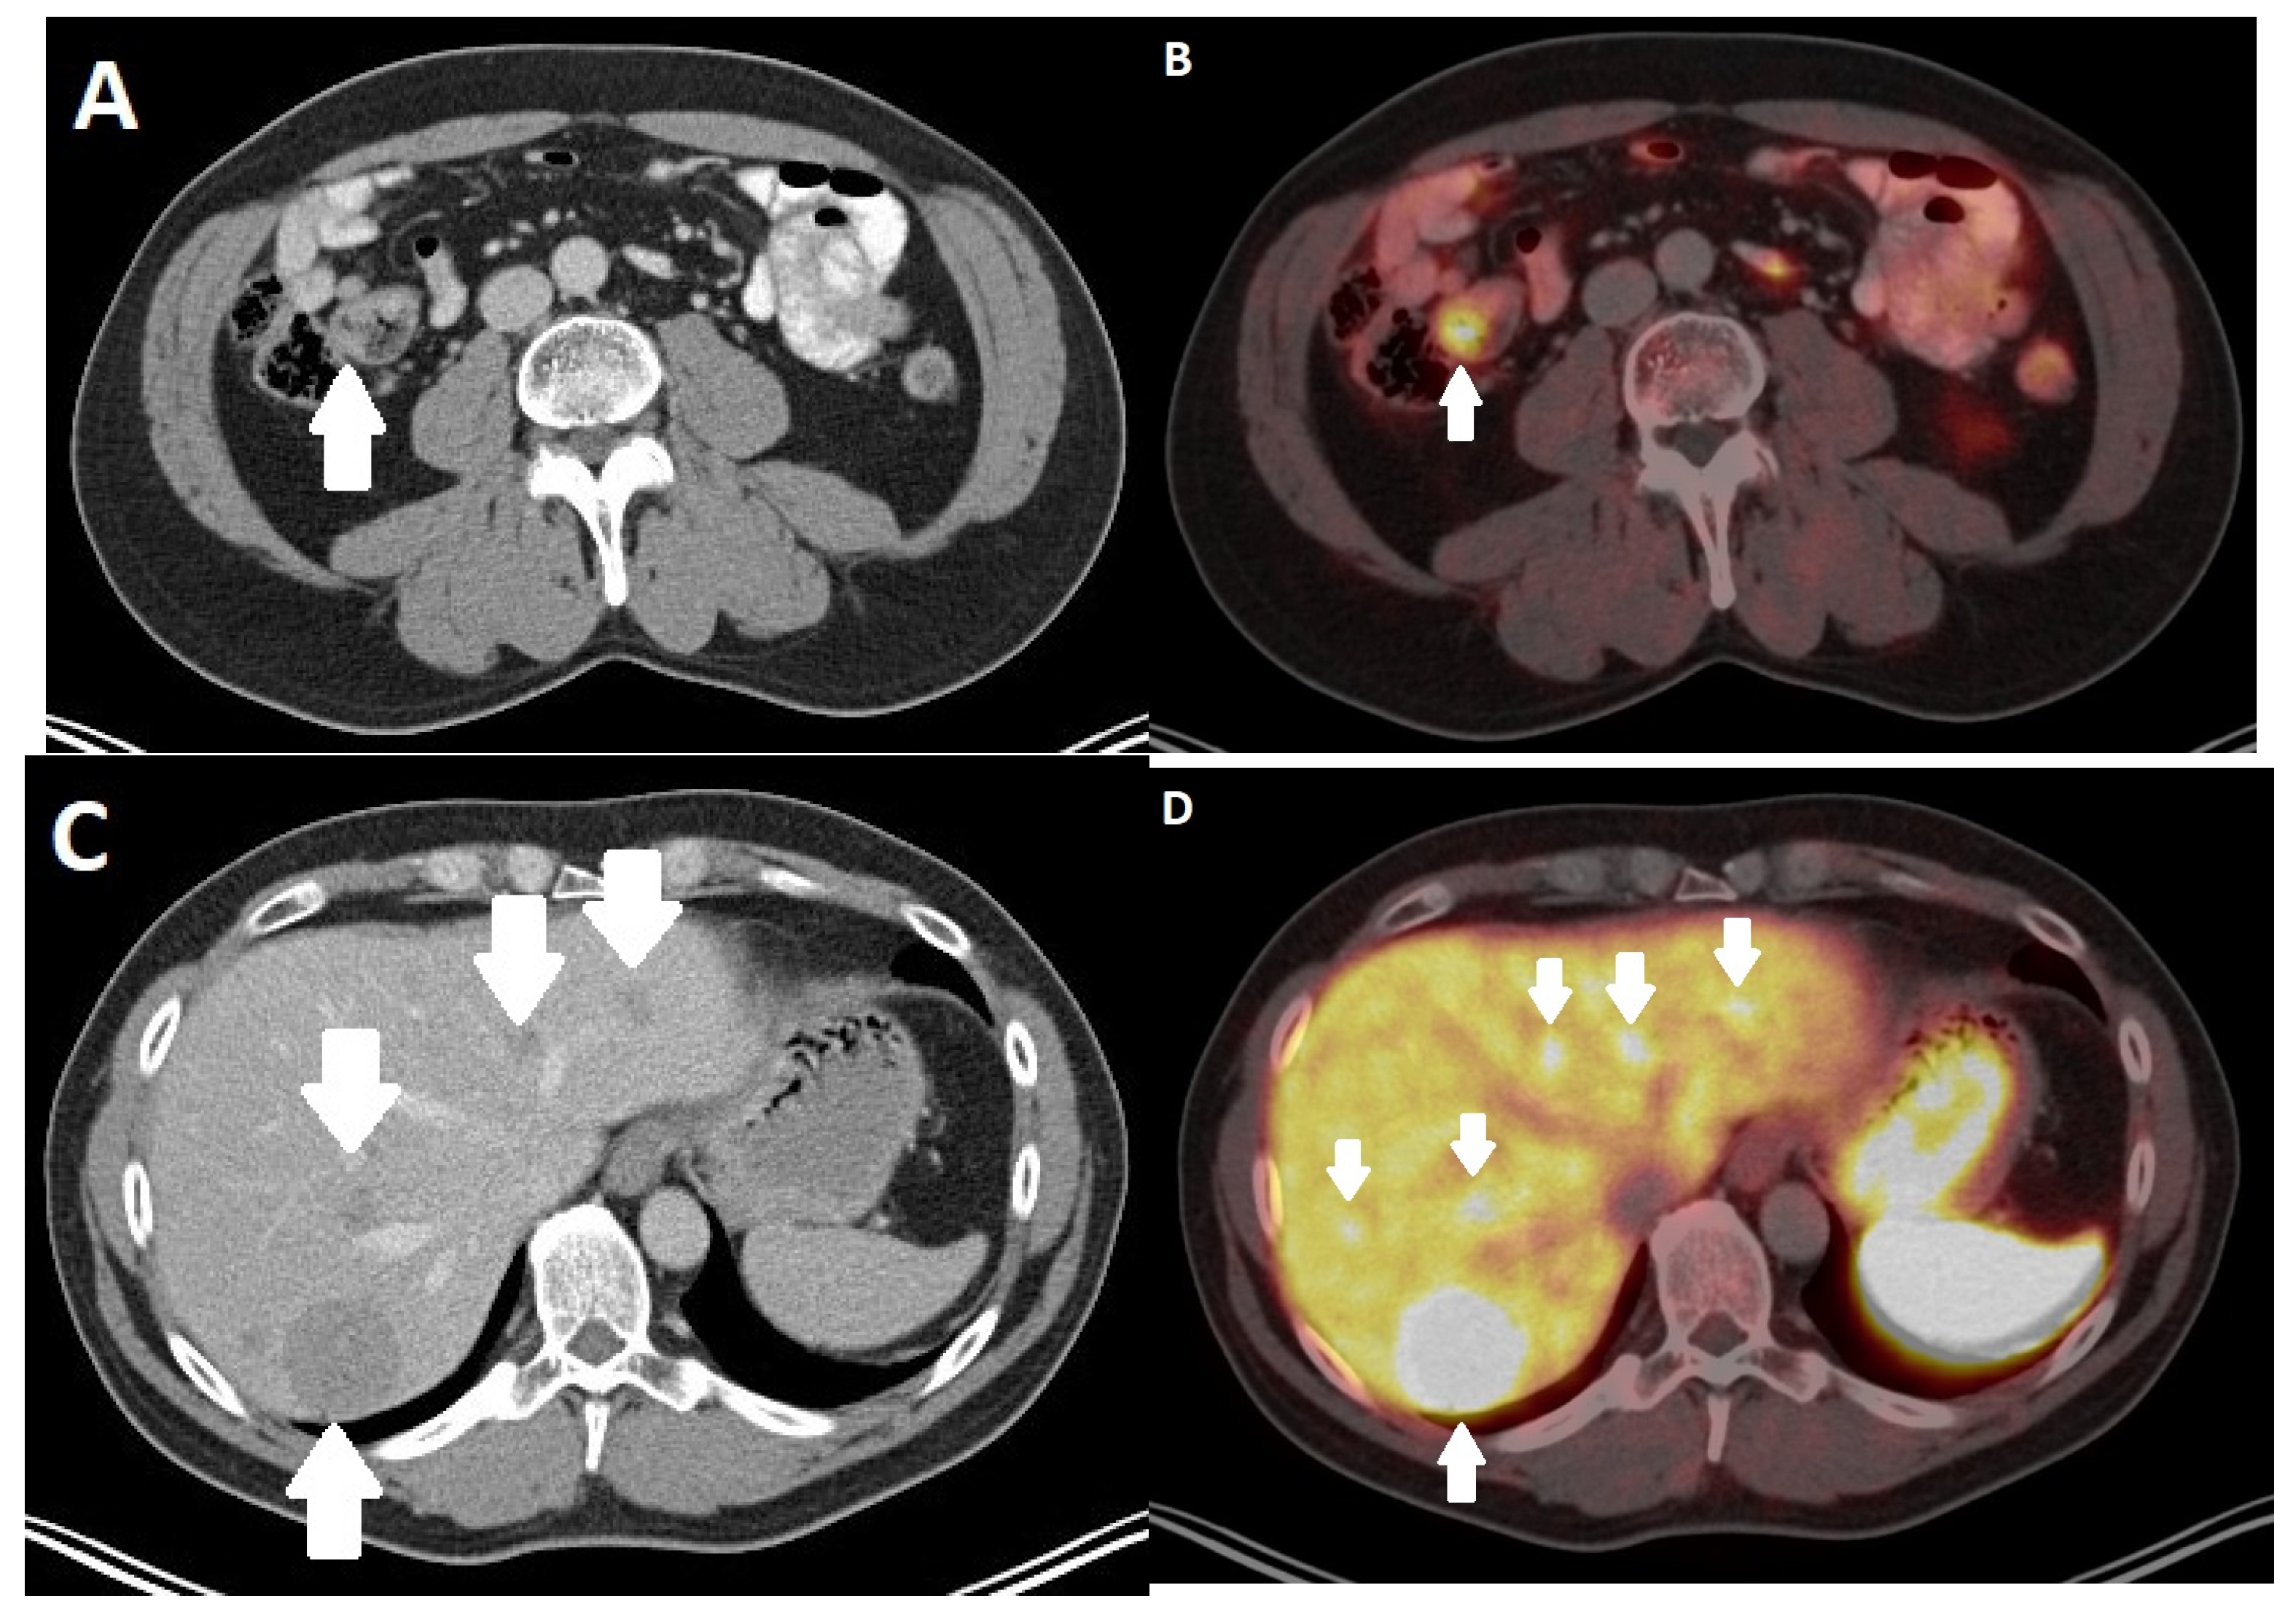

4. Nuclear Medicine Imaging Techniques

- Geijer, H.; Breimer, L.H. Somatostatin receptor PET/CT in neuroendocrine tumours: Update on systematic review and meta-analysis. Eur. J. Nucl. Med. Mol. Imaging 2013, 40, 1770–1780. [Google Scholar] [CrossRef]

- Treglia, G.; Sadeghi, R.; Giovinazzo, F.; Galiandro, F.; Annunziata, S.; Muoio, B.; Kroiss, A.S. PET with Different Radiopharmaceuticals in Neuroendocrine Neoplasms: An Umbrella Review of Published Meta-Analyses. Cancers 2021, 13, 5172. [Google Scholar] [CrossRef]

- Fortunati, E.; Argalia, G.; Zanoni, L.; Fanti, S.; Ambrosini, V. New PET Radiotracers for the Imaging of Neuroendocrine Neoplasms. Curr. Treat. Options Oncol. 2022, 23, 703–720. [Google Scholar] [CrossRef]

- Yoo, J.; Kim, S.H.; Jeon, S.K.; Bae, J.S.; Han, J.K. Added value of [(68)Ga]Ga-DOTA-TOC PET/CT for characterizing pancreatic neuroendocrine neoplasms: A comparison with contrast-enhanced CT and/or MRI in a large study cohort. Eur. Radiol. 2021, 31, 7734–7745. [Google Scholar] [CrossRef]

- Sadowski, S.M.; Neychev, V.; Millo, C.; Shih, J.; Nilubol, N.; Herscovitch, P.; Pacak, K.; Marx, S.J.; Kebebew, E. Prospective Study of 68Ga-DOTATATE Positron Emission Tomography/Computed Tomography for Detecting Gastro-Entero-Pancreatic Neuroendocrine Tumors and Unknown Primary Sites. J. Clin. Oncol. Off. J. Am. Soc. Clin. Oncol. 2016, 34, 588–596. [Google Scholar] [CrossRef]